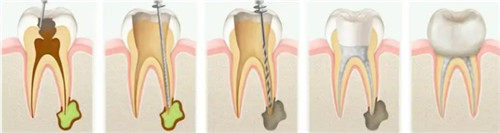

根管治疗

对于牙髓炎和根尖周炎等引起的牙痛和下颚疼痛,根管治疗是一种有效的治疗方法。

根管治疗通过清除受感染的牙髓组织,填充根管并封闭冠部,从而消除炎症、降低疼痛。根管治疗后,牙齿可能会变得脆弱,需要佩戴牙冠进行保护。